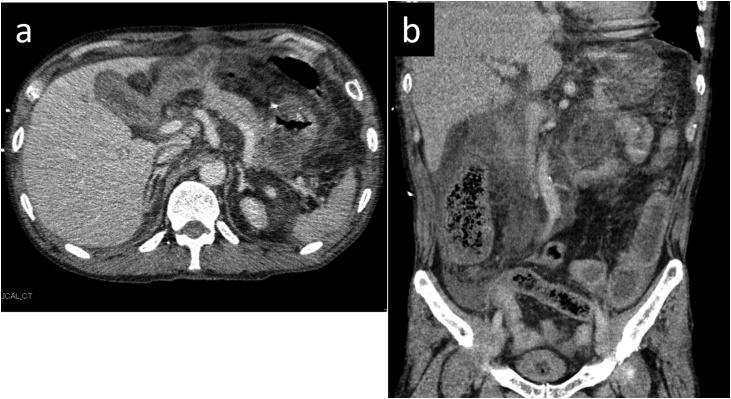

A 64-years-old man presented with upper abdominal pain and reported a history of PD 5 years prior to presentation. Contrast-enhanced computed tomography revealed an edematous pancreatic remnant with inflammation of the surrounding tissue, and he was diagnosed with acute pancreatitis. His condition worsened, and he was transferred to our hospital the following day. He was admitted to the intensive care unit to manage respiratory and circulatory insufficiency. Although his condition improved, an abdominal abscess was identified, and necrosectomy was performed on day 43 of hospitalizaiton. We carefully removed as much necrotic tissue as was possible without injury to the pancreaticojejunal anastomosis and the ascending colon. Inflammation gradually subsided, and he was discharged on day 111 of hospitalization. The last drain was removed in day 133 of admission to our hospital. Pancreatitis and abdominal abscess have not recurred until the time of writing this paper.